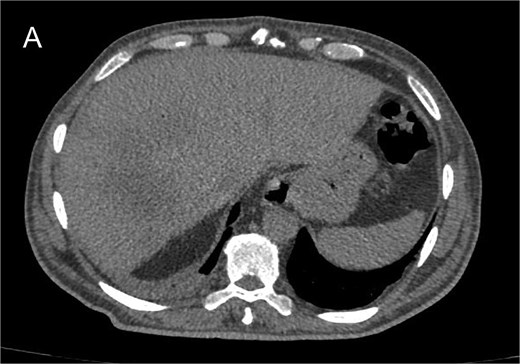

After one month, the patient remained asymptomatic. Follow-up CT revealed a marked decrease in intra-hepatic collections (Fig. 5).

Non-contrast abdominal CT scan at 1-month postoperatively showing significant reduction in intrahepatic collection.